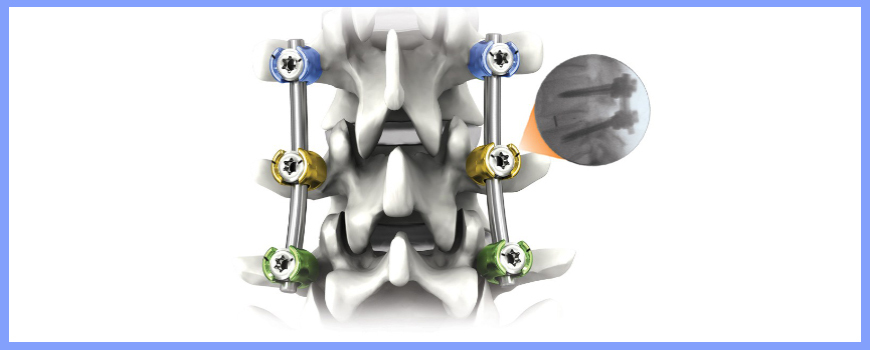

These fractures can be treated very well with the help of Pedicular screw system. This system and the C arm image intensifier equipment are very useful to correct and fix these vertebral fractures in the best possible position. After the spinal fixation, it is possible for the patients to sit and walk very early and the fixation gives very good pain relief.